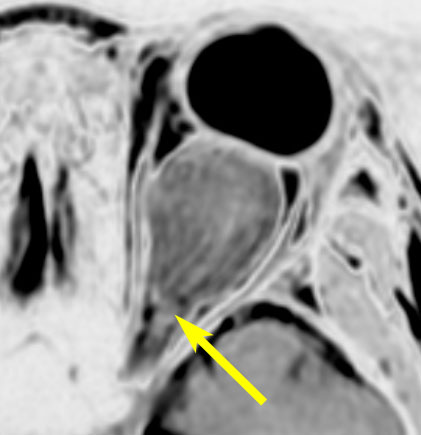

眼窩内に限局する視神経膠腫:神経鞘腫と鑑別が難しいもの

主訴は進行性の眼球突出です。視力低下は軽度で,視野欠損は左眼の下半分でした。入院前の画像では眼窩内神経鞘腫を疑う画像でした。

しかし,CISSの画像では中枢側の視神経との連続性があり,これではじめて視神経膠腫と診断できました。もちろん毛様細胞性星細胞腫です。眼球,眼球運動,眼瞼の動きを温存して腫瘍を眼球後極から切断して全摘出しました。